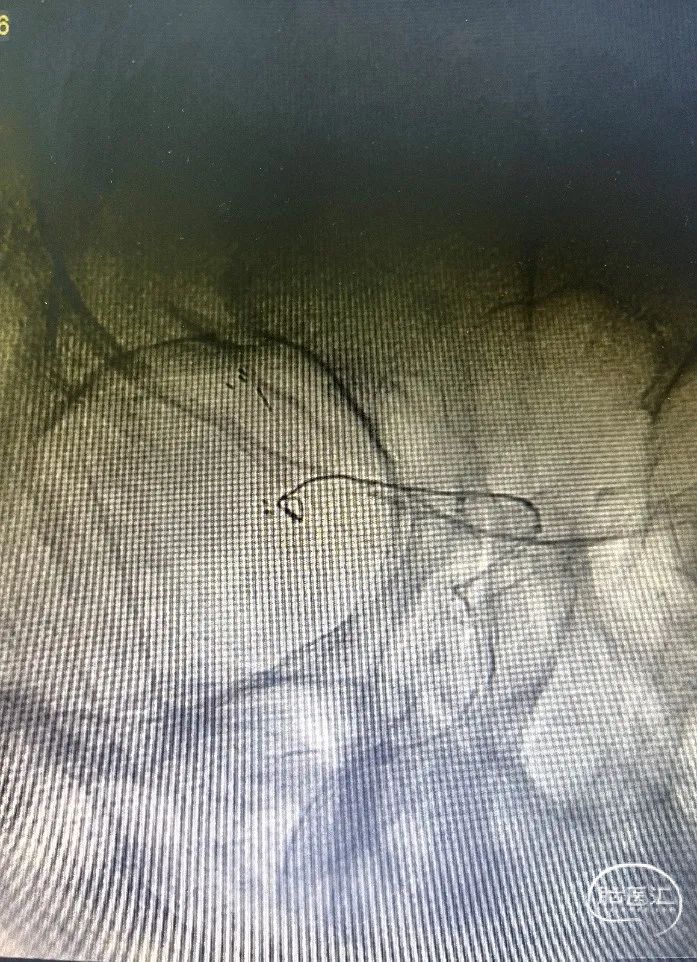

DSA:右侧大脑中动脉分叉部动脉瘤,约3*5mm,颈宽约5mm,伴上下干起始部扩张。

大脑中动脉近端M1直径2.82mm,远端1.83mm,上干1.85mm,下干1.7mm。

大脑中动脉下干置入3*24mm Atlas支架,使用Target 360 Ultra 2mm*4cm;弹簧圈栓塞动脉瘤。行造影观察血流通畅。(如下动态影像)

穿第一枚支架网眼于上干置入3*15mm Atlas支架

使用第二枚弹簧圈Target 360 Nano 1.5mm*4cm栓塞动脉瘤,造影显示动脉瘤瘤腔内有滞留,考虑到是未破裂动脉瘤,故结束手术。(如下动态影像)

术后造影

治疗后正位减影造影,动脉瘤基本致密栓塞,患者术后无明显不适,术后阿司匹林,波立维双抗。目前一般状况良好。(如下动态影像)

1. 本例患者为右侧大脑中动脉分叉部动脉瘤伴上下干瘤样扩张,使用两个Atlas支架作交叉“Y”型支架,释放简单,支架贴壁良好,既可有效栓塞动脉瘤,又可有效保护大脑中动脉重要分支。